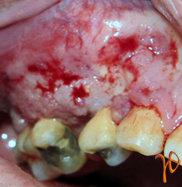

Οι πιο συχνές βλάβες στο στόμα είναι τα αποστήματα, τα οποία όταν οφείλονται σε μικροβιακές λοιμώξεις δοντιών της άνω γνάθου μπορούν να εκδηλώνονται και στην υπερώα (Εικόνα 3). Η θεραπεία τους προϋποθέτει την θεραπεία του υπεύθυνου δοντιού.

Εικόνα 3. α. Απόστημα που οφείλεται σε γομφίο οδόντα (βέλος), β. Απόστημα που οφείλεται σε τομέα οδόντα (βέλος).